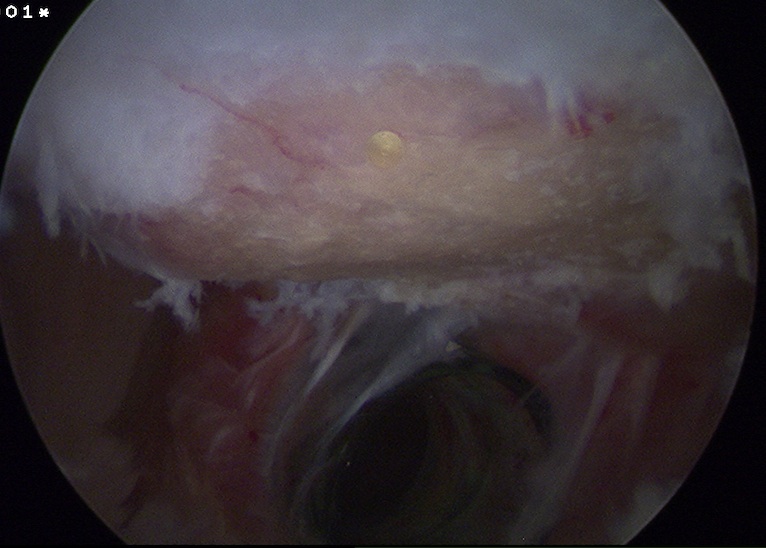

Arthroscopy

Normal insertion onto humeral neck